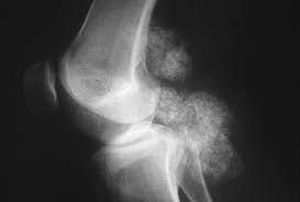

Diagnosis and treatment??

It's sarcoma

Synovial sarcoma